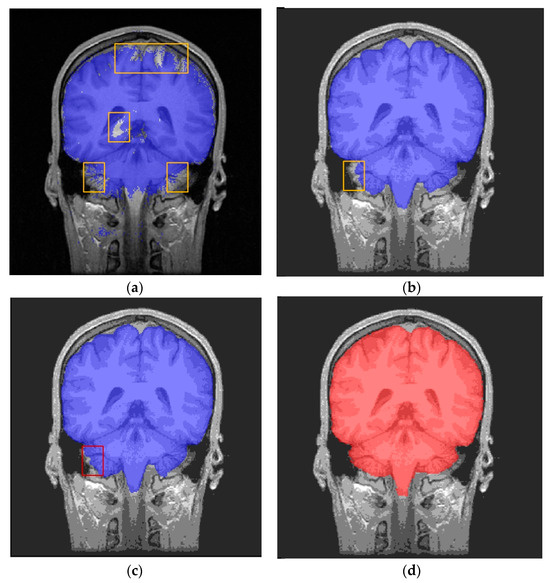

2.2. Full Image Information Mining with a K-Means Cluster Preprocessing

2.3. Hybrid-U-Net Framework

3.2. Results